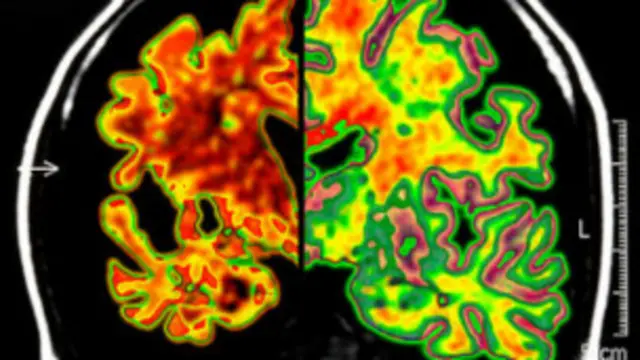

Dejeneretif sinir sistemi hastalıklarında beyin dokusunun ölümünü engelleyen ilk kimyasal bileşimin keşfi, Alzheimer, Parkinson ve Huntington hastalıklarının tedavisi açısından tıp dünyasında heyecan yarattı.

Bu süreç beyinde bütün nöronlarda tekrarlanınca hareket ya da hafıza kaybı, hatta ölümle sonuçlanan tahribatlara yol açıyor.

Science Translational Medicine dergisinde yayımlanan araştırma, beyni süngere dönüştüren prion hastalıklara sahip olan farelerde ciddi hafıza ve hareket kaybı görüldüğünü ve 12 haftada öldüklerini ortaya koydu.

Fakat bu kimyasal bileşimin verildiği farelerde beyin dokusunda hiçbir kayıp görülmedi.